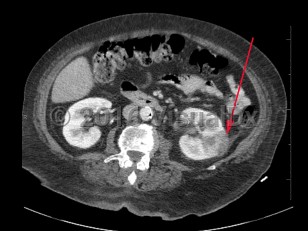

Pyelonephritis

Patients present with a triad of flank pain, fever, and nausea / vomiting. There are often associated symptoms including dysuria, urinary urgency, or urinary frequency. The patient can also have concurrent noninfectious complicating conditions like renal calculi and renal infarction. Gross hematuria may occasionally be seen. Patients with spinal cord injury or dementia may present atypically, but fever is expected to be present in cases of pyelonephritis. Examination may reveal costovertebral angle tenderness.

Complications of pyelonephritis include progression to sepsis and septic shock and, in rare cases, papillary necrosis, renal abscess, and perinephric abscess.